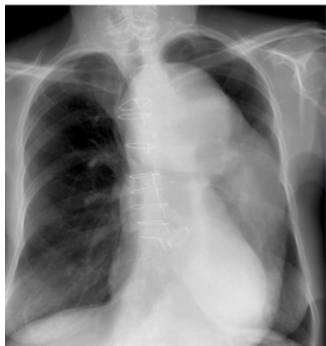

What is this? and what causes it?

viral pna caused by influenza